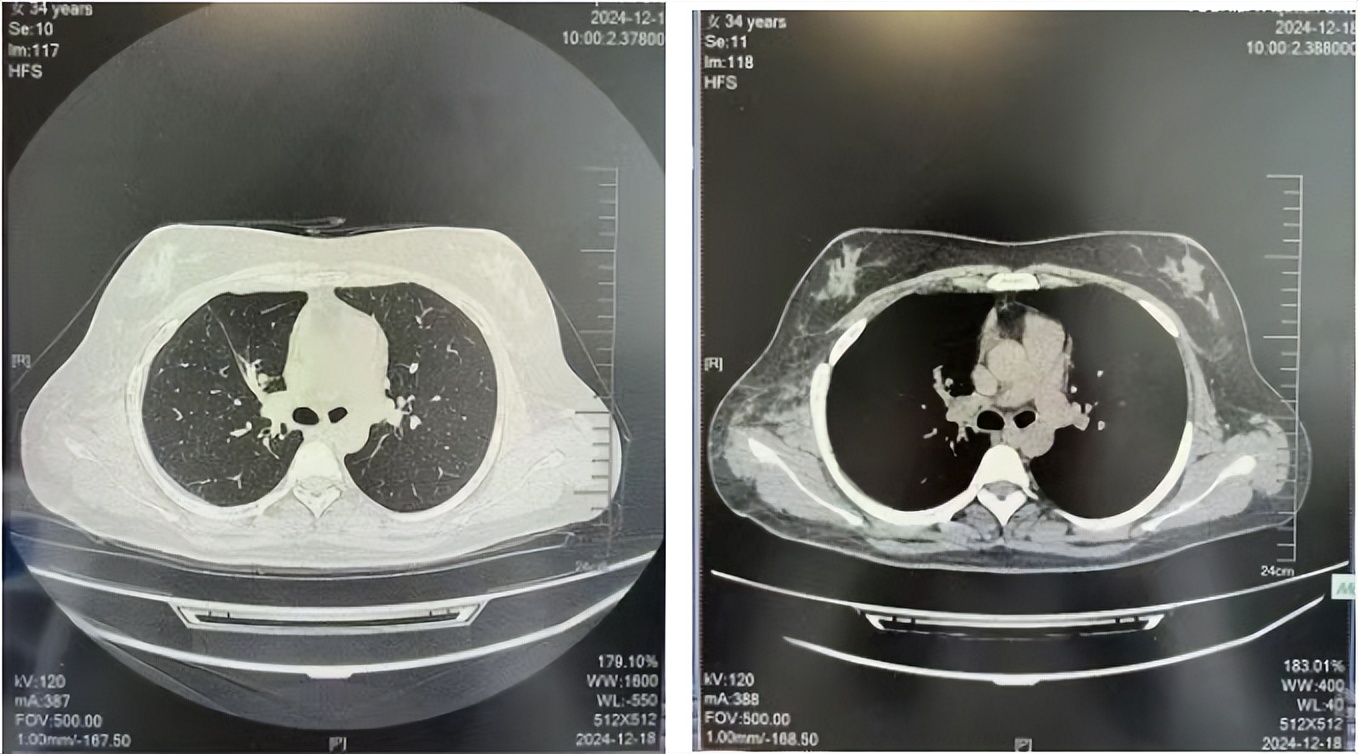

2024.12

2023年2月20日基线检查

2024年6月复查PR(最佳疗效)

2024年12月复查维持PR

2025年3月复查维持PR